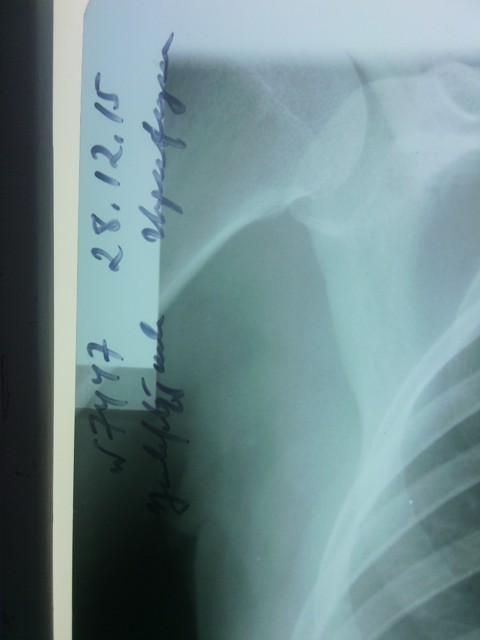

Բաժանմունքի վարիչը բացատրել է, որ այդ վիճակով դուրս գրվել չիկարող. անհրաժեշտ է կատարել ռենտգեն հետազոտություն, որից հետո որոշել դուրս գրման հարցը: Համայցից հետո հիվանդը ենթարկվել է ռենտգեն հետազոտության, որի ժամանակ հայտնաբերվել է թոքաբորբ: Կրկին կատարվել է թերապևտի կոնսուլտացիա, որը թոքերում լսել է թացխզոցներ, առավելապես՝ ձախից: Հիվանդին և նրա ամուսնուն բացատրվել է, որ կարիք կա հետագա բուժումը շարունակելու Երևանի 3-րդ կարգի մանկաբարձական բաժանմունքներից որևէ մեկում: Տրվել է ուղեգիր: Հիվանդի ամուսինը ցանկացել է իր մեքենայով տեղափոխել հիվանդին Երևան: Միաժամանակ նշենք, որ «Զարիշատ (Արամ) Մարտին Մկրտչյանի անվան Արմավիրի ԲԿ» ՓԲԸ մանկաբարձական բաժանմունքում հիվանդը մնացել է 39 ժամ, և Երևան գնալու պահին նրա վիճակը եղել է բավարար:

Կից տեղադրվում է նաև «Զարիշատ (Արամ) Մարտին Մկրտչյանի անվան Արմավիրի ԲԿ» ՓԲԸ-ում կատարված ռենտգեն նկարը: